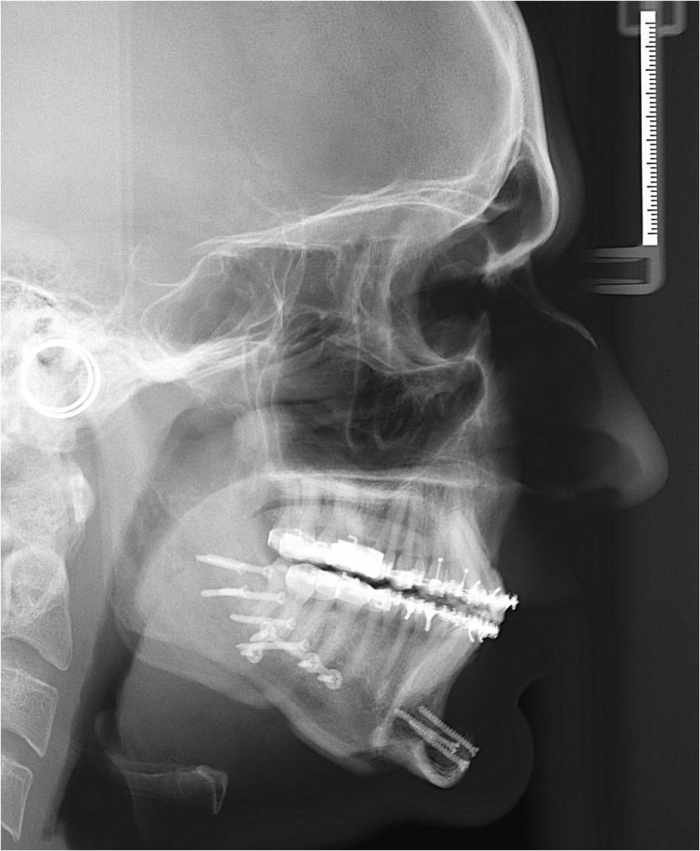

Telerradiografia inicial